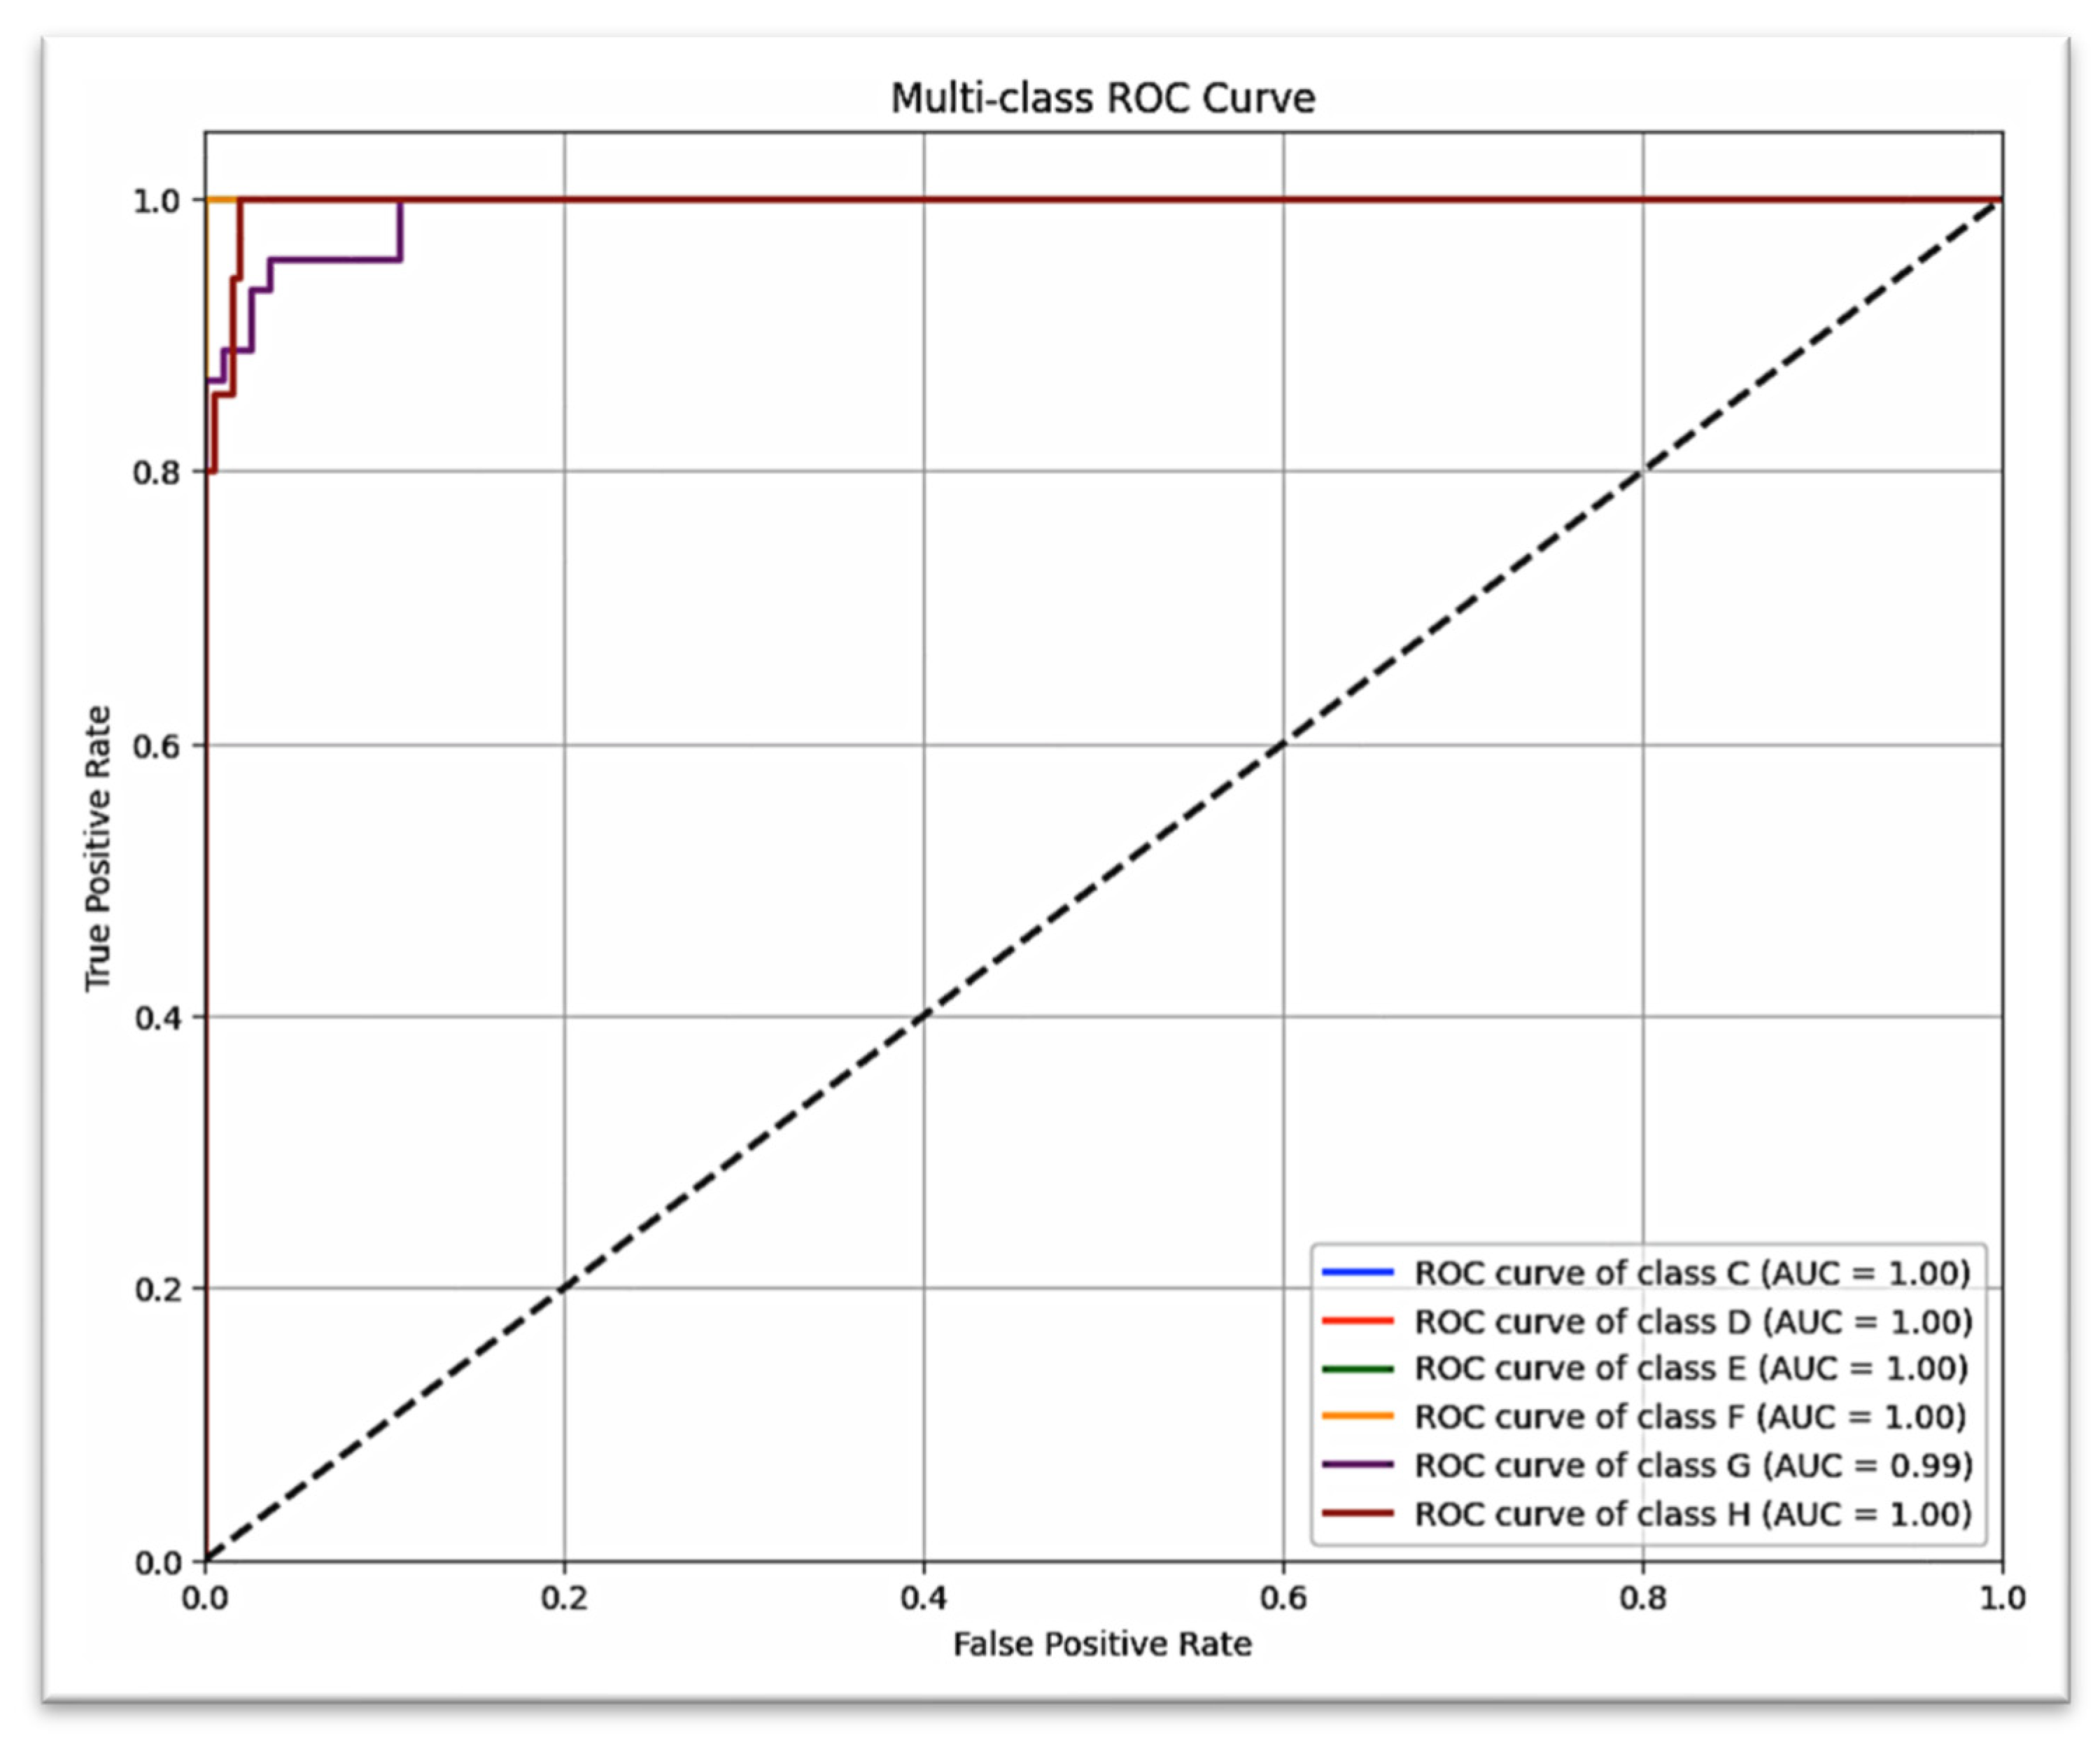

The confusion matrix for canine prediction graphed in

Figure 7 shows that almost all of the strong diagonal elements indicate the correct stage predicted stage. A similar multi-class ROC curve (

Figure 8) suggests that the model is robust to all stages of canine development (AUC = 1.00 for all but G stages, which scored AUC = 0.99).